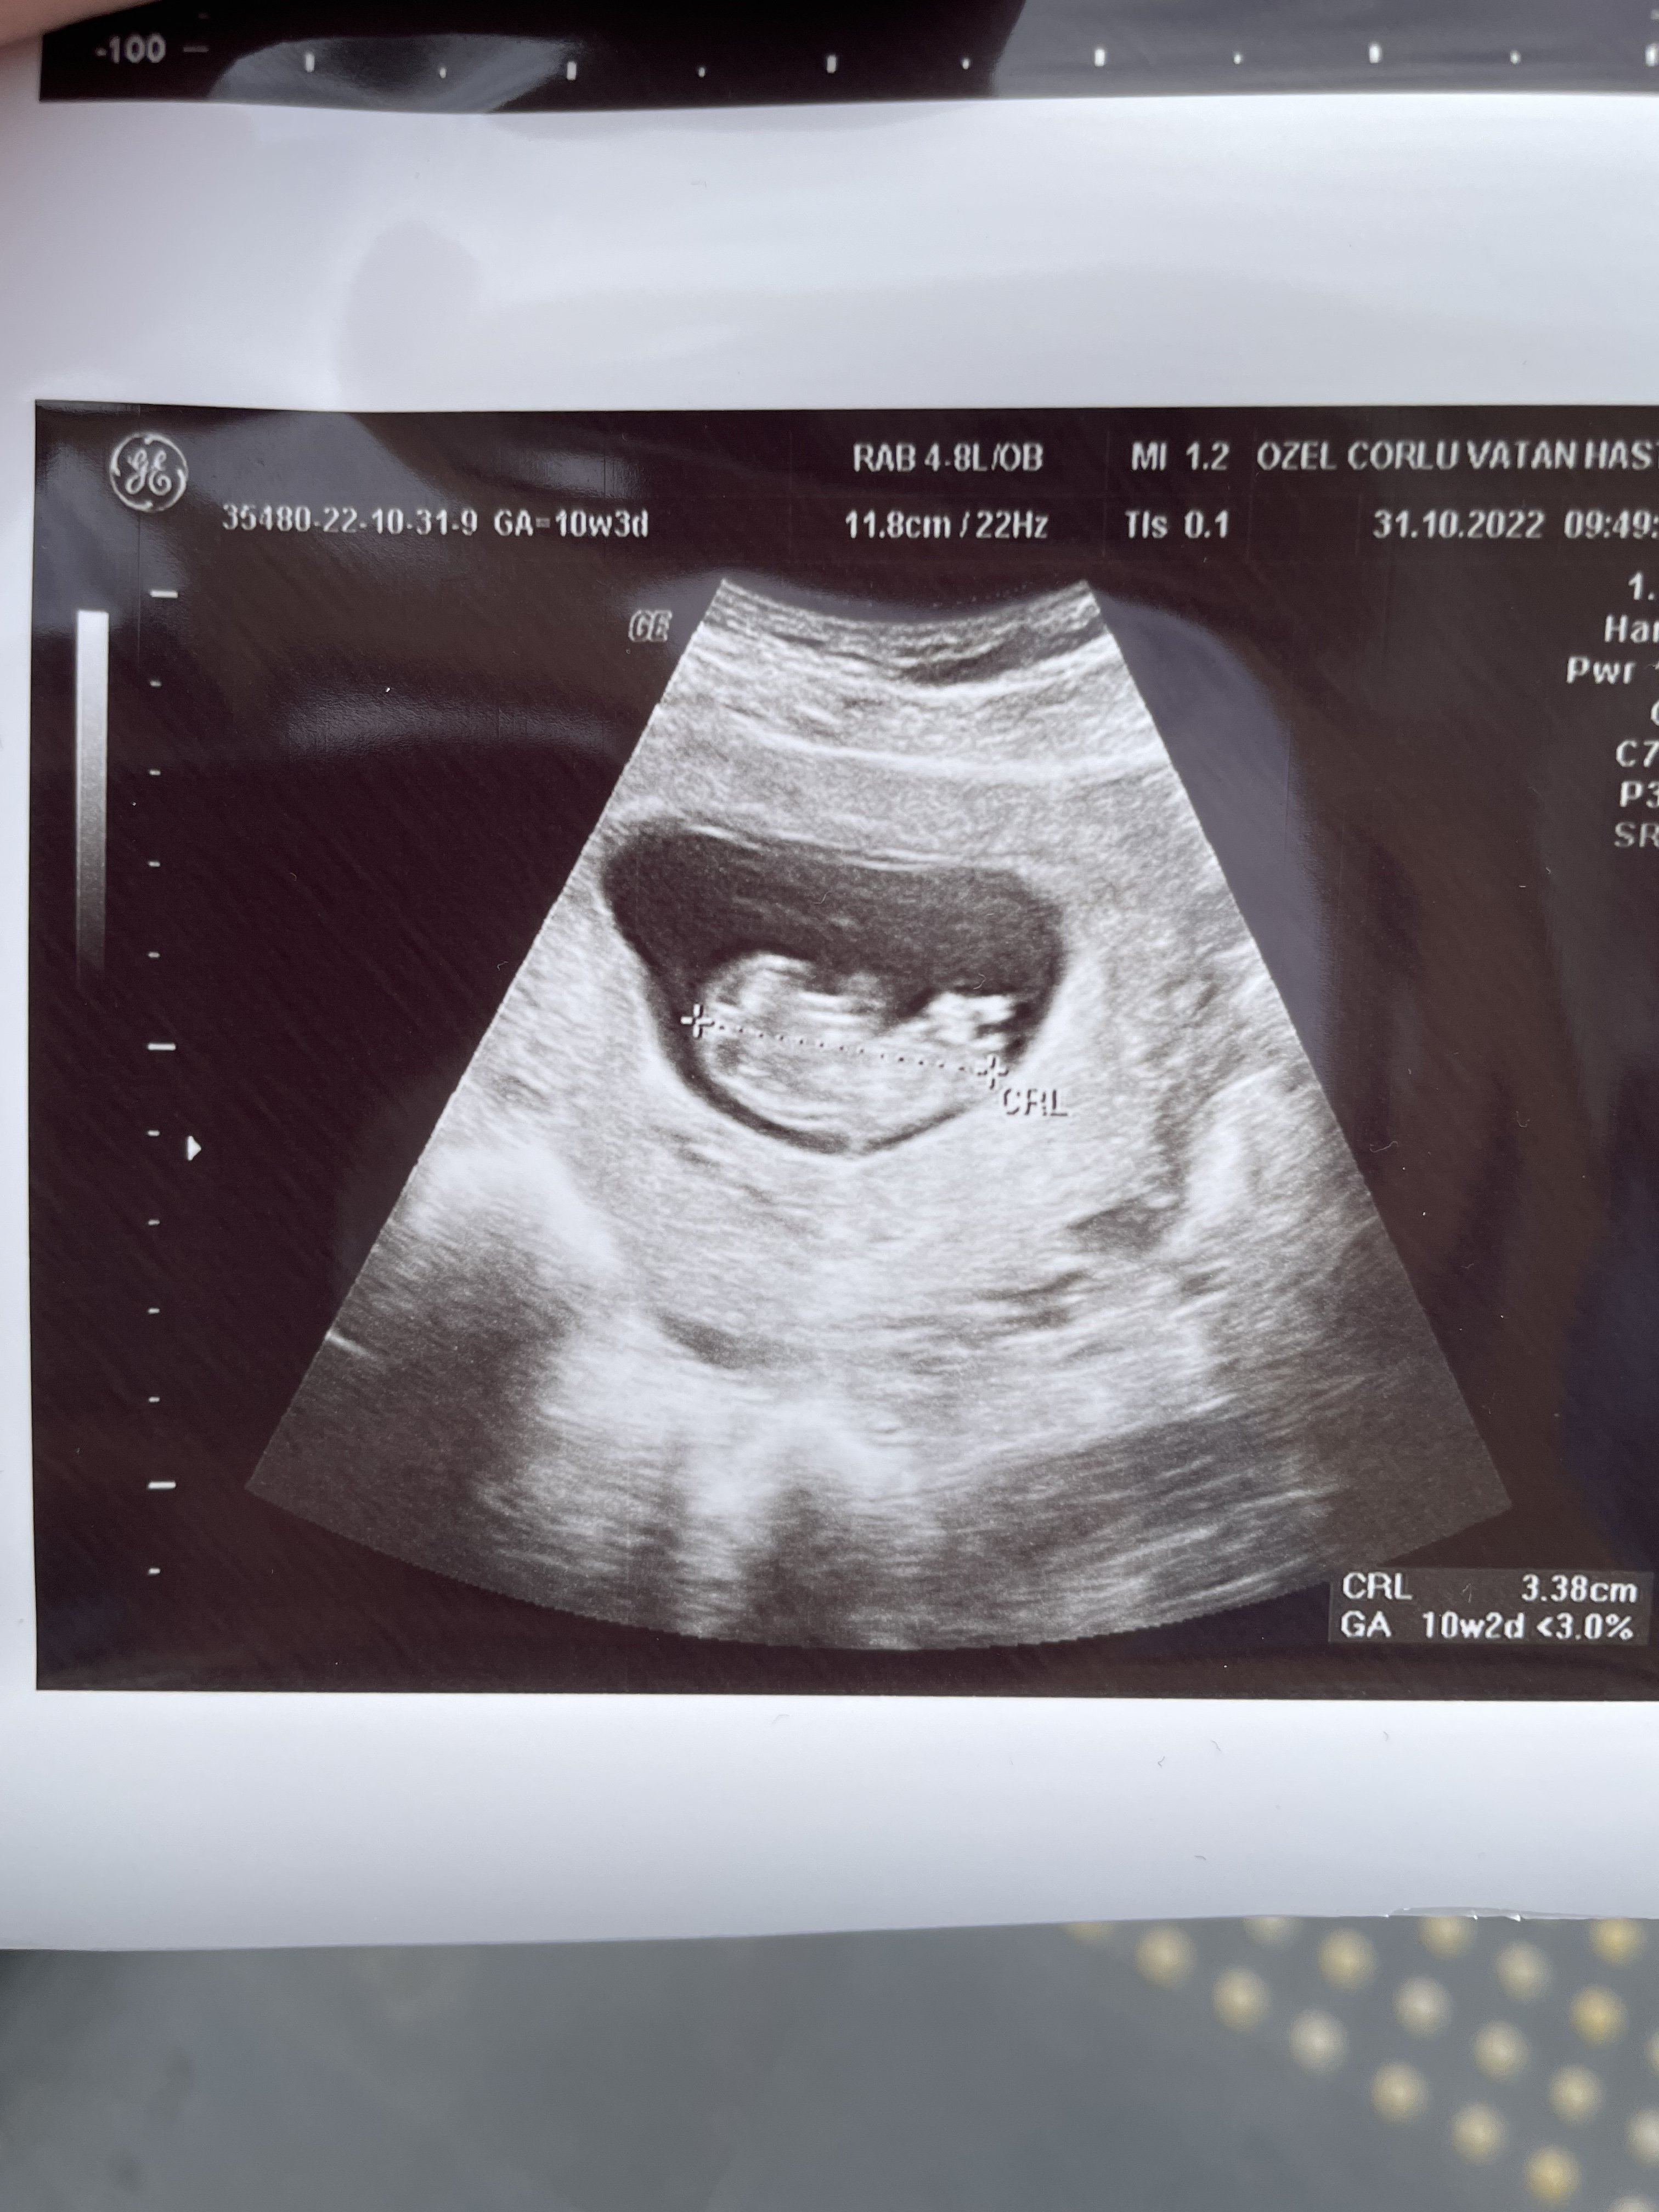

Bu arada gözlerim beni yanıltmıyor ise yukarı doğru çıkıntı mevcut erkek gibi görüyorum ama çok net te değil hayatım. Tabi ki gaybı Allah bilir biz sadece bu olabilir diye söyleriz bilgin olsun 🙂 Yanılıyor olabilirim.

Tamam bi tanem Rabbim sağlıklı şekilde kucağına almayı nasip etsin. İnşallah tahminimiz doğru çıkar KIZ bi tanem öyle görüyorum 🙂